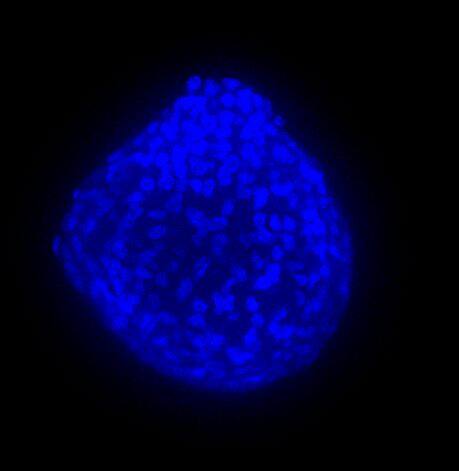

我们采用 CrestOptics X-Light V3 转盘共聚焦结合 Prime BSI 相机(Photometrics,像素尺寸 6.5 um)进行采集。我们比较了使用 20 倍空气物镜(CFI Plan Apo Lambda,尼康,0.7 NA 和 1mm WD)和 25 倍硅油物镜(CFI Plan Apo Lambda S,尼康,1.05 NA 和 0.55 mm WD)进行的采集。在图 A 中,我们展示了从总共 150 um 的 Z 堆栈中获得的最大强度投影 (MIP) 图像;特别是,使用 20 倍空气物镜和 25 倍硅油物镜获得了相同的球体。图 B 显示了使用两种物镜获得的 3D 球体同一区域的放大。

使用 20 倍空气物镜和使用 25 倍硅油物镜获得的图像之间的比较(图 A、B 和 C)突出了基于生物应用的透镜选择的重要性。从 20 倍到 25 倍的转换导致分辨率提高(基于 25 倍的 NA 大于 20 倍 NA),这当然会影响图像质量,并且还会导致光折射减少。事实上,浸油通过用更高折射率的介质代替透镜和盖玻片之间的空气间隙,大大提高了显微镜的分辨率,从而减少了光的折射。

在 3D 成像中,样品的折射率与其浸没介质的折射率相匹配对于深层组织观察至关重要。硅酮浸油非常适合透过厚厚的生物样本进行成像;它与细胞和封固剂的折射率非常吻合,与使用普通 20 倍空气物镜获得的图像相比,减少了球面像差,产生了更亮、分辨率更高的图像。

图 A:使用 20 倍空气物镜(顶部)和 25 倍硅油物镜(底部)获得的肿瘤球体 Z 堆栈的最大密度投影 (MIP)。活细胞用钙黄绿素(绿色)标记,死细胞用 PI(红色)标记。细胞核用 Hoechst(蓝色)染色。比例尺:100 um。这些图像是使用 CrestOptics X-Light V3 转盘获取的。